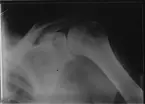

Röntgenfotografi taget av Oscar Karlowitch Larsson vid Åminne, Stäket eller Sockholm.